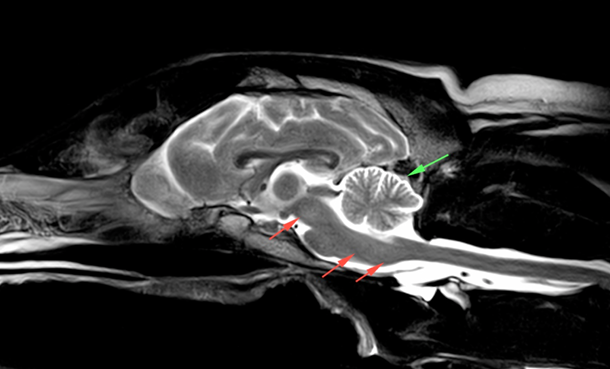

Midsagittal Mr Brain Images Midsagittal Mr Brain Images T2 Weighted Download Scientific Diagram